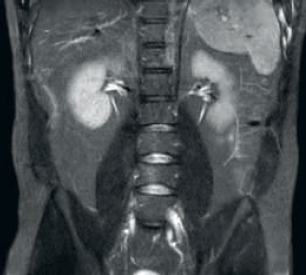

Result: Improved SNR and image resolution

Increased consistency and enhanced image quality dStream RF receive technology digitizes the MR signal directly in the RF coil, resulting in an increase of up to 40% more SNR* throughout the whole image volume. Simplified workflow and improved throughput Posterior coil integrated into the tabletop eliminates coil handling in 60% of exams. Lightweight conforming anterior coils and singlehanded, single cable coil connections add to operational ease.